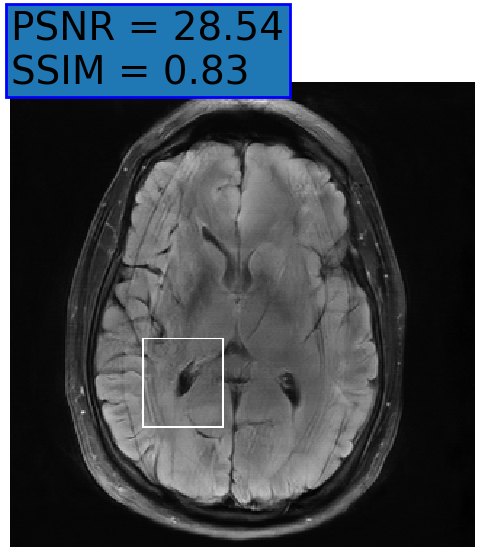

(c) baseline

Refer to caption

Figure 3: Reconstructions results. Rows 1 and 3: Examples of comparing the ground truth (GT) fully sampled image to the reconstructed images obtained by the three models (1-3), NPB-REC, baseline, E2E-VarNet trained with Dropout, and the NPB-REC std. map at accelerations R=4𝑅4R=4, R=8𝑅8R=8, respectively. Rows 2 and 4: The corresponding annotated ROIS of Nonspecific white matter lesions.

Fig. 3 presents examples of reconstruction results obtained by (1) our NPB-REC approach, (2) the baseline, and (3) Monte Carlo Dropout, for equispaced masks with two different acceleration rates R=4𝑅4R=4 and R=8𝑅8R=8. The reconstructed images predicted by the three models are smoother than the reference image. This is due to the fact that all the models were trained with SSIM loss, which tends to produce overly smooth reconstructions while preserving the diagnostic content and the anatomical features Sriram et al. (2020a). These images can be enhanced by dithering the image by adding a small amount of random Gaussian noise to produce a more textured reconstruction, as proposed in Sriram et al. (2020b).

Table 1 presents the mean PSNR and SSIM metrics, calculated over the whole inference set, for the three models. Our NPB-REC approach achieved significant improvements over the other methods in terms of PSNR and SSIM (Wilcoxon signed-rank test, pmuch-less-than\ll1e-4, except for SSIM values in line W, R=4𝑅4R=4 where they are roughly the same for NPB-REC and Baseline). The improvement in the reconstruction performance can be noted both quantitatively from the metrics, especially for masks with acceleration rate R=8𝑅8R=8, and qualitatively via the images of annotations, where our results show less smoothness than those obtained by Dropout.